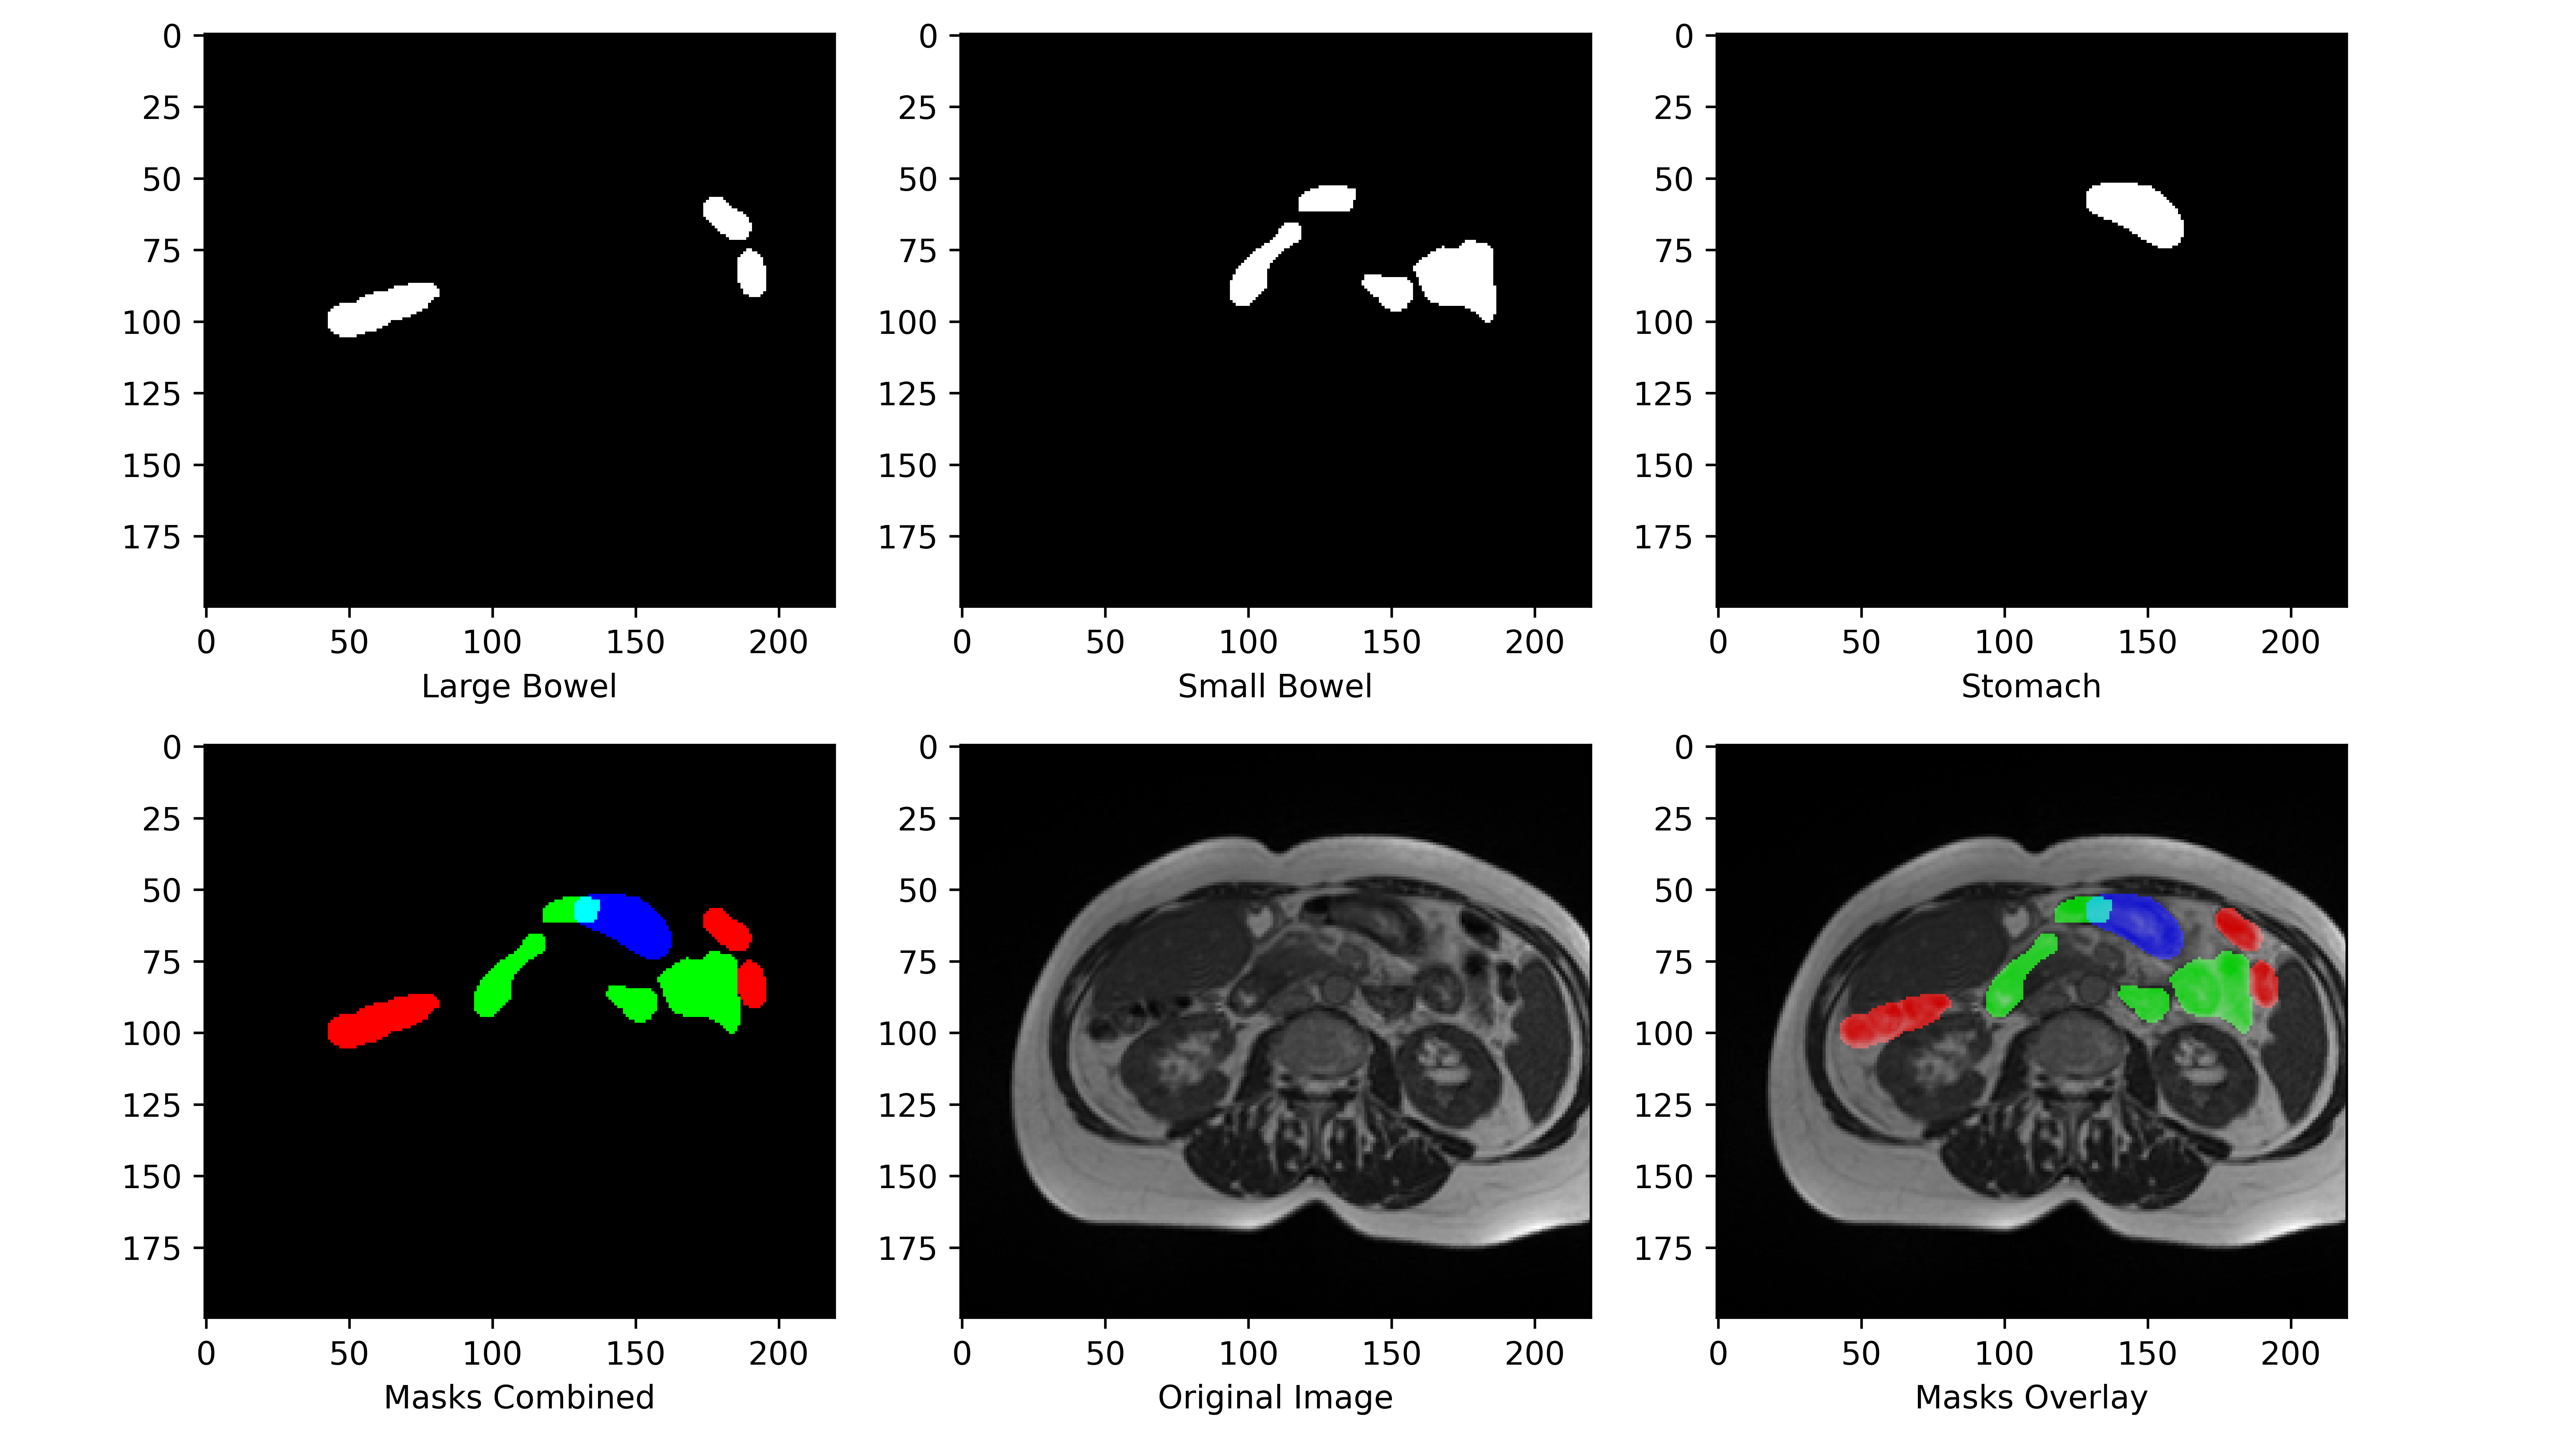

The aim of this study is to use the existing knowledge and apply it to the problem of GI tract segmentation. There is a lack of research done on the segmentation of GI tract organs. This study aims to provide a new baseline using different backbones of U-Net architectures in order to segment organs such as stomach, large Bowel and small Bowel (Fig. 1). The task of this research is to find the best architecture to create masks for a scan that highlights the Large Bowel, Small Bowel, and Stomach. Generally, the process of applying deep learning to such tasks starts with collecting the data and effectively pre-prossessing the data to be fed into the model to create useful predictions. The next section discusses the dataset used in this research.

Refer to caption

Figure 1: Dataset (scans with masks of organs)